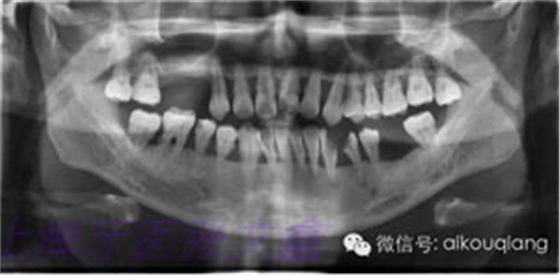

下面這張X光片是比較典型的牙周炎的X光片,該患者全口所有的牙齒都呈現(xiàn)出2~3度的松動(dòng)?;颊攥F(xiàn)在感覺無法用牙齒咀嚼。坦白地講,牙周炎發(fā)展到這種程度,很多時(shí)候醫(yī)生也束手無策了。為了保留更多的牙槽骨,醫(yī)生會(huì)不得不拔掉那些嚴(yán)重松動(dòng)的牙齒。